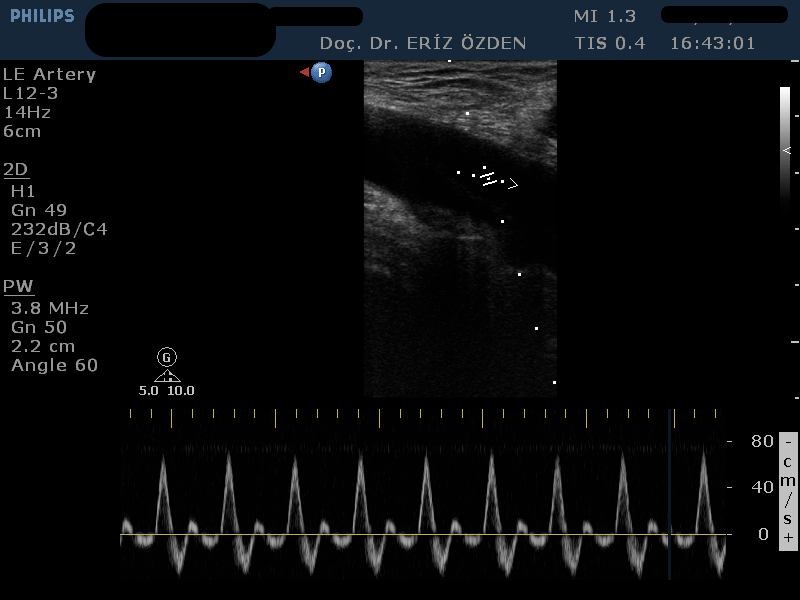

Bacak atar damarlarının darlıklarının, tıkanmalarının, yetmezliklerinin araştırılmasında kullanılır. Bir tek bacak için yaklaşık 20-30 dakika kadar süren bir tetkiktir. İncelemenin herhangi bir ön hazırlığı yoktur.